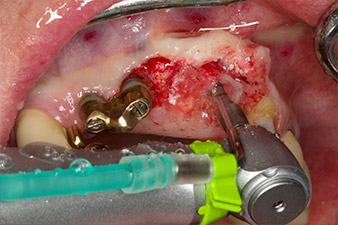

След първичното оздравяване, меките тъкани са оформени посредством базално разположения мост. Два месеца по-късно, обработваното поле е изложено на палатинална алвеоларна инцизия (Фиг 2). Размерите на алвеоларната кост са достатъчни в позиция 22. Фигури 2 и 4 показват препарацията на имплантното ложе, нарязващия винт и имплатирането, използвайки Implantmed.

пилотното изпиляване е извършено с новия Implantmed и обратен наконечник WS-56 L

Фиг. 2: Два месеца по-късно, пилотното изпиляване е извършено с новия Implantmed и обратен няконечник WS-56 L (програма P1, съотношение 1:1). Охлаждането е е осъществено чрез шлауха за физиологичен разтвор, позициониран отляво (за потребители, работещи с дясна ръка).